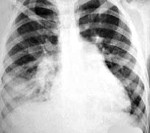

- Рентген. Рентгенография легких в 2-х проекциях позволяет определить типичную локализацию аспирационной пневмонии в так называемых зависимых сегментах легкого: задних верхнедолевых и верхних нижнедолевых сегментах (при аспирации содержимого в горизонтальном положении) или нижних долях (при нахождении пациента во время аспирации в горизонтальной позиции). Кроме этого, определяются ателектазы легкого, очаги деструкции в легочной паренхиме, скопление газа над экссудатом в полости плевры.

- Рентгенография грудной клетки имеет ведущее диагностическое значение при кровохаркании. Следует помнить, что обнаруженные на рентгенограмме патологические изменения не обязательно будут указывать на истинный источник кровохарканья. Поэтому, выявленную на рентгенографии патологию, следует уточнить при помощи компьютерной томографии. Однако, если стандартная рентгенограмма грудной клетки не обнаруживает каких-либо дисфункций или отклонений, проводить томографию лёгких или компьютерную томографию в качестве дополнительного исследования не следует.